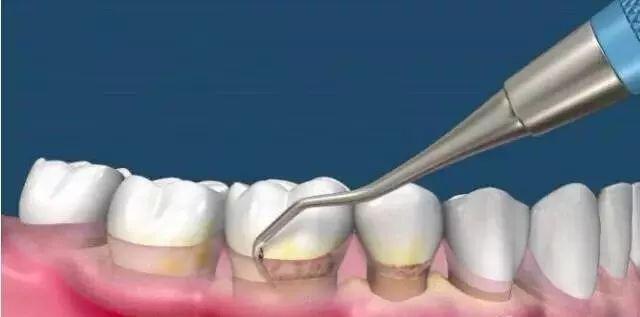

调节牙周(非必需)

正畸前,医生需要你的牙周适合矫正,如果牙周不好勉强进行矫正的话可能会出现牙槽骨吸收等问题,所以牙周不好的童鞋需要在正畸前进行牙周调节。同样的,有蛀牙什么的也需要先补好。